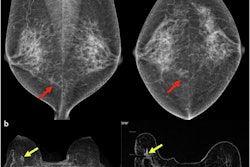

AI-supported mammography finds more breast cancers during screening and reduces interval cancer diagnosis by 12% in the years following screening, suggest findings published on 29 January in The Lancet.

A team led by Dr. Kristina Lång, PhD, from Lund University and Skåne University Hospital in Sweden, found that AI-supported mammography screening showed consistently favorable outcomes compared with double reading. These include finding a comparable number of interval cancers and having higher sensitivity.

The Mammography Screening with Artificial Intelligence (MASAI) trial is currently the only randomized controlled trial evaluating AI-supported mammography screening to have reported results and is the first such study to be completed. Published results showed a 44% reduction in screen-reading workload for radiologists and a 29% increase in cancer detection without increasing false positives.

AI-assisted mammography led to noninferior interval cancer rates versus double reading, as well as superior sensitivity and comparable specificity.